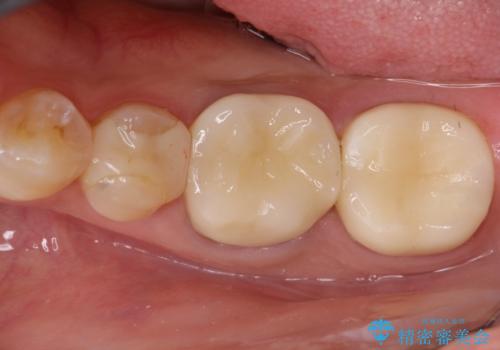

【メタルフリー】オールセラミッククラウン

オールセラミッククラウン(st)にて修復しております。

根管治療も合わせて行なっているため、期間がかかっております。